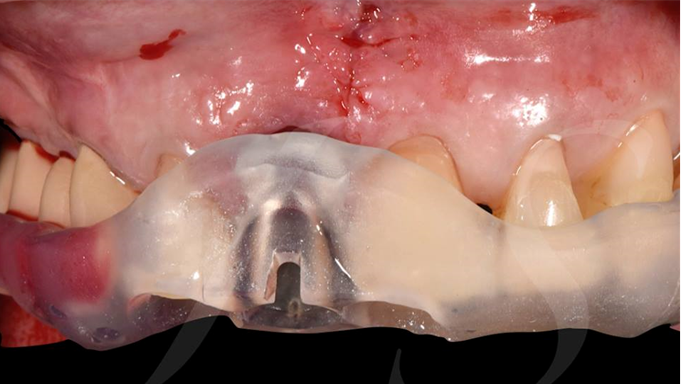

Clinical case: Extraction, immediate placement & loading using

R2GATE solution in aesthetic zone

- Courtesy of Dr. Jong-Cheol Kim, Korea-

Dr. Jong Cheol Kim, immediate loading, digital guided surgery, Digital ONE-DAY Implant, maxillary anterior, #21, guided surgery, immediate loading, AnyRidge, R2GATE, Mega ISQ, MEG Torq, R2GATE Full Surgical Kit

AnyRidge implant system, R2 Guide, R2GATE Full Surgical Kit, Mega ISQ